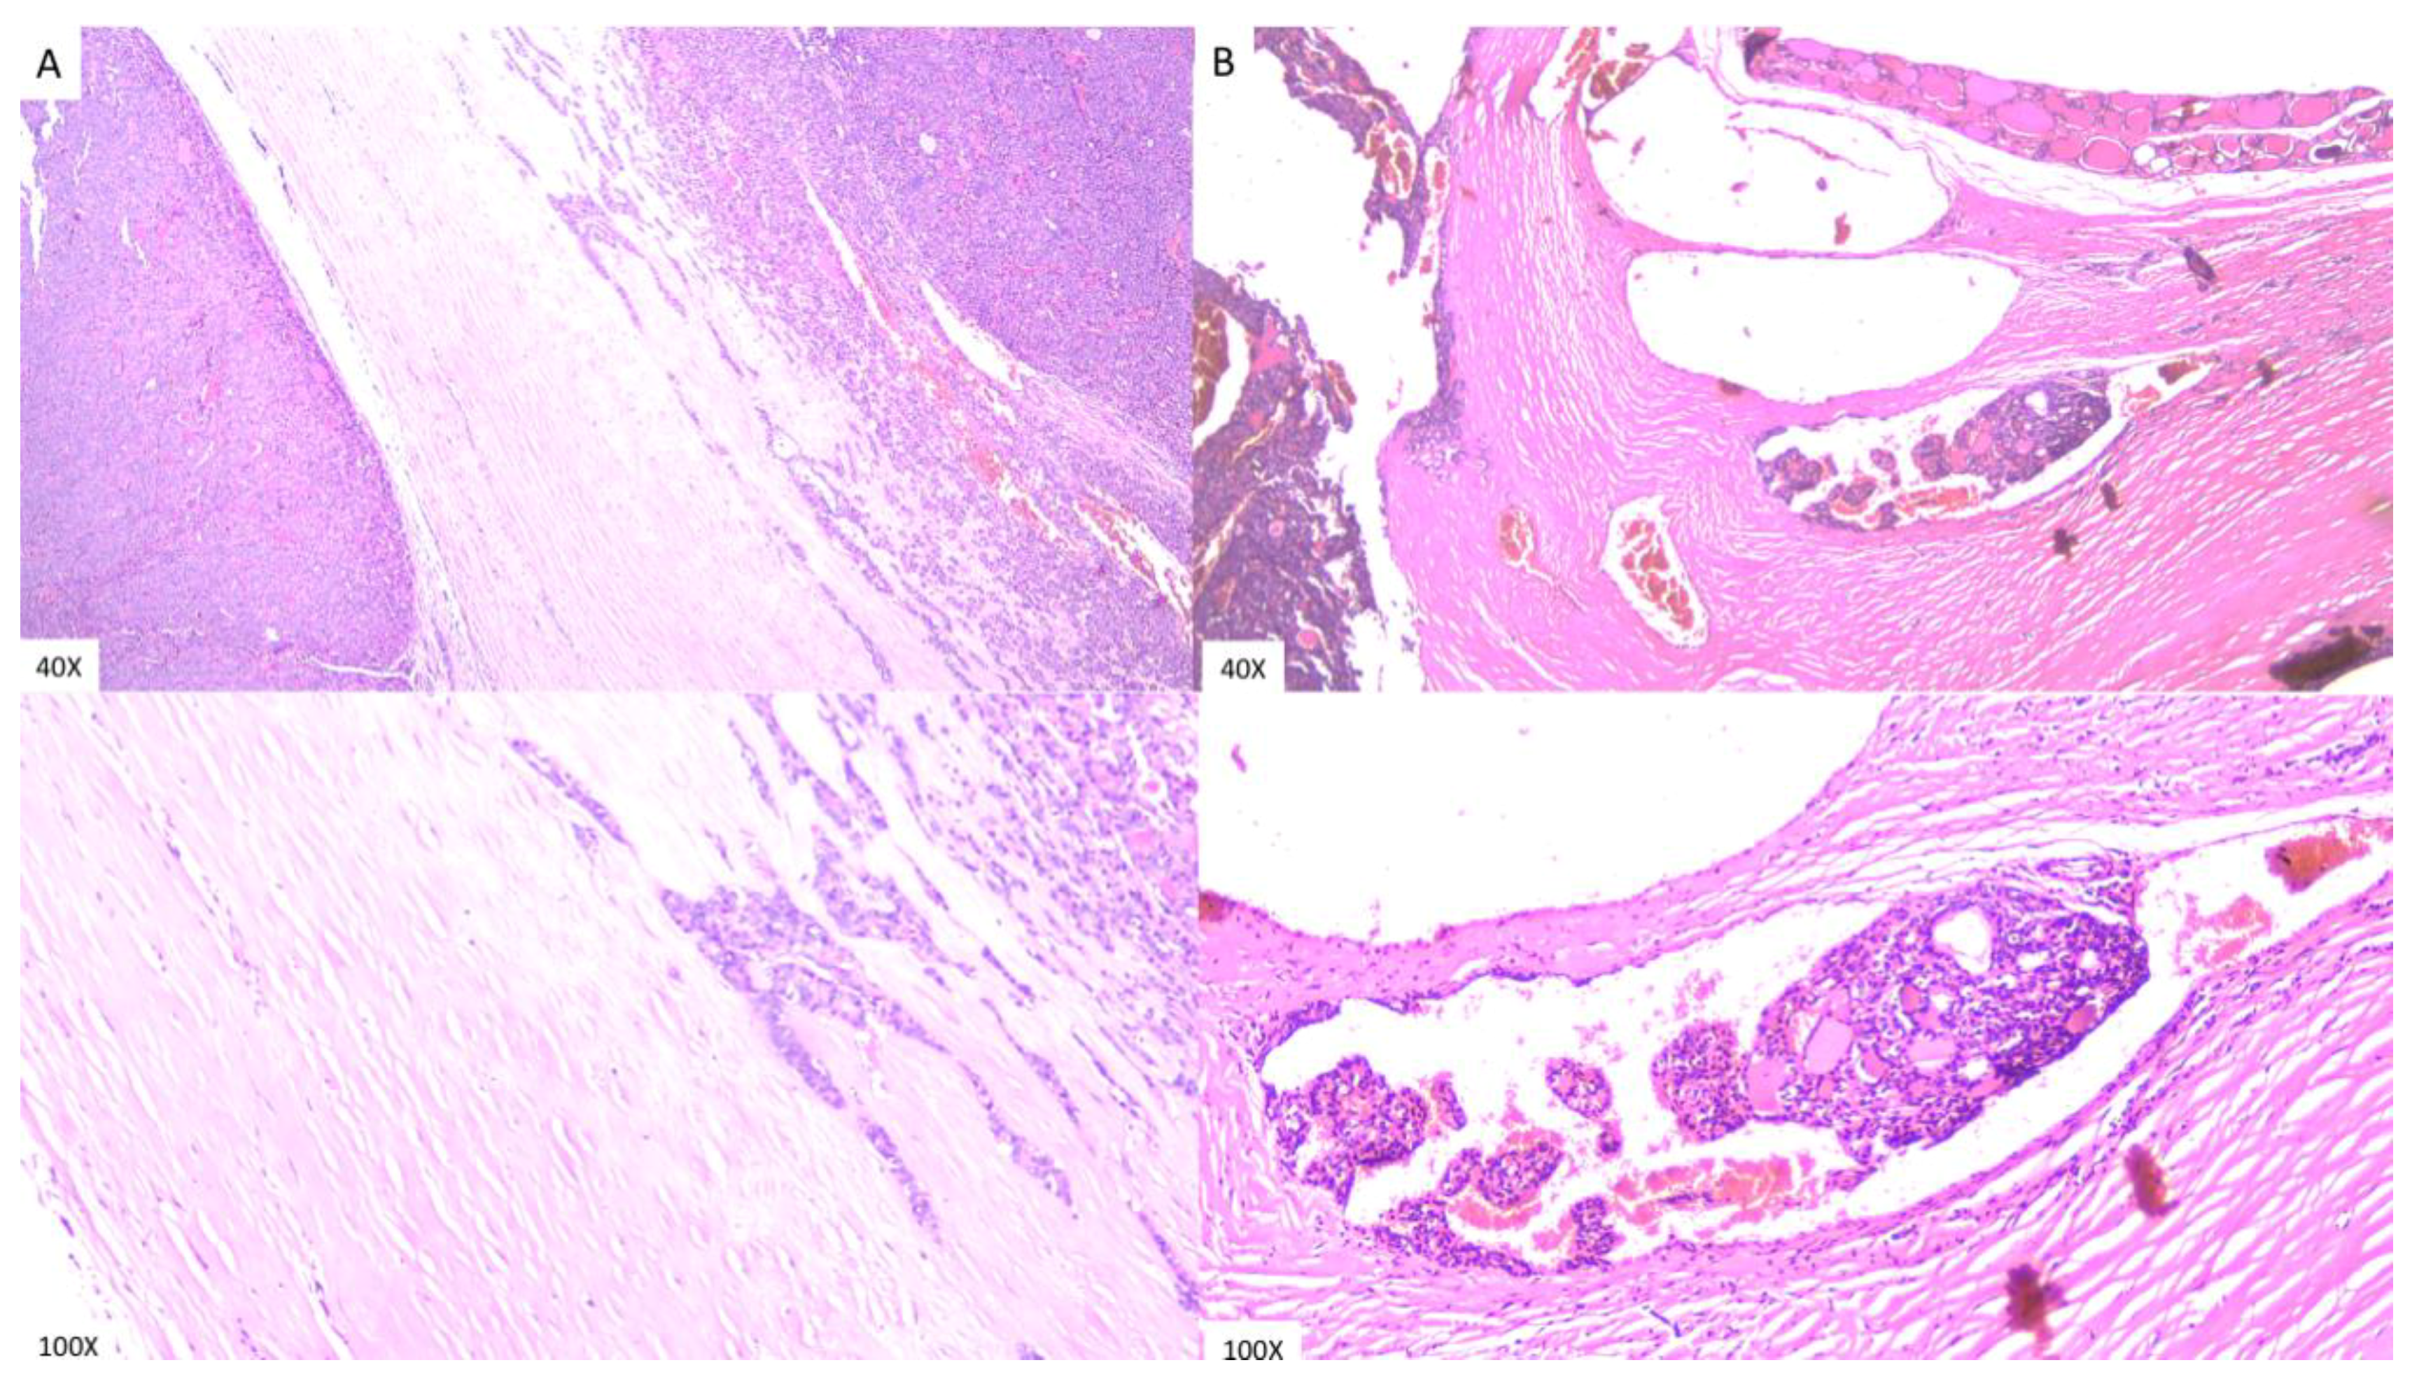

2.2. Diagnosis